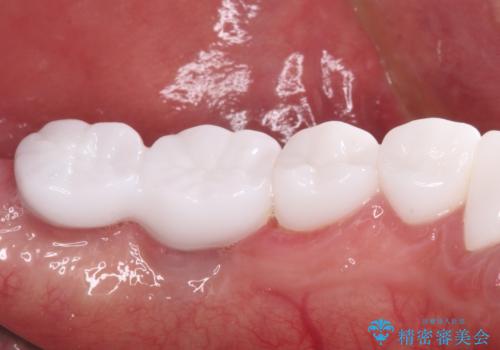

とにかく作り物のような真っ白な歯にしたい フルジルコニアクラウンによる補綴治療

不自然なくらい真っ白にしたいとのことでしたので、透明感のないフルジルコニアクラウンを用いて補綴することとしました。

本来、あまりにも不自然な歯となるため、フルジルコニアクラウンを前歯に使用することは、咬合力が強すぎる場合を除き、ほとんどありません。

それでも、色調、形態ともに不自然なくらい真っ白な歯をご希望でしたので、患者様には大変満足していただきました。